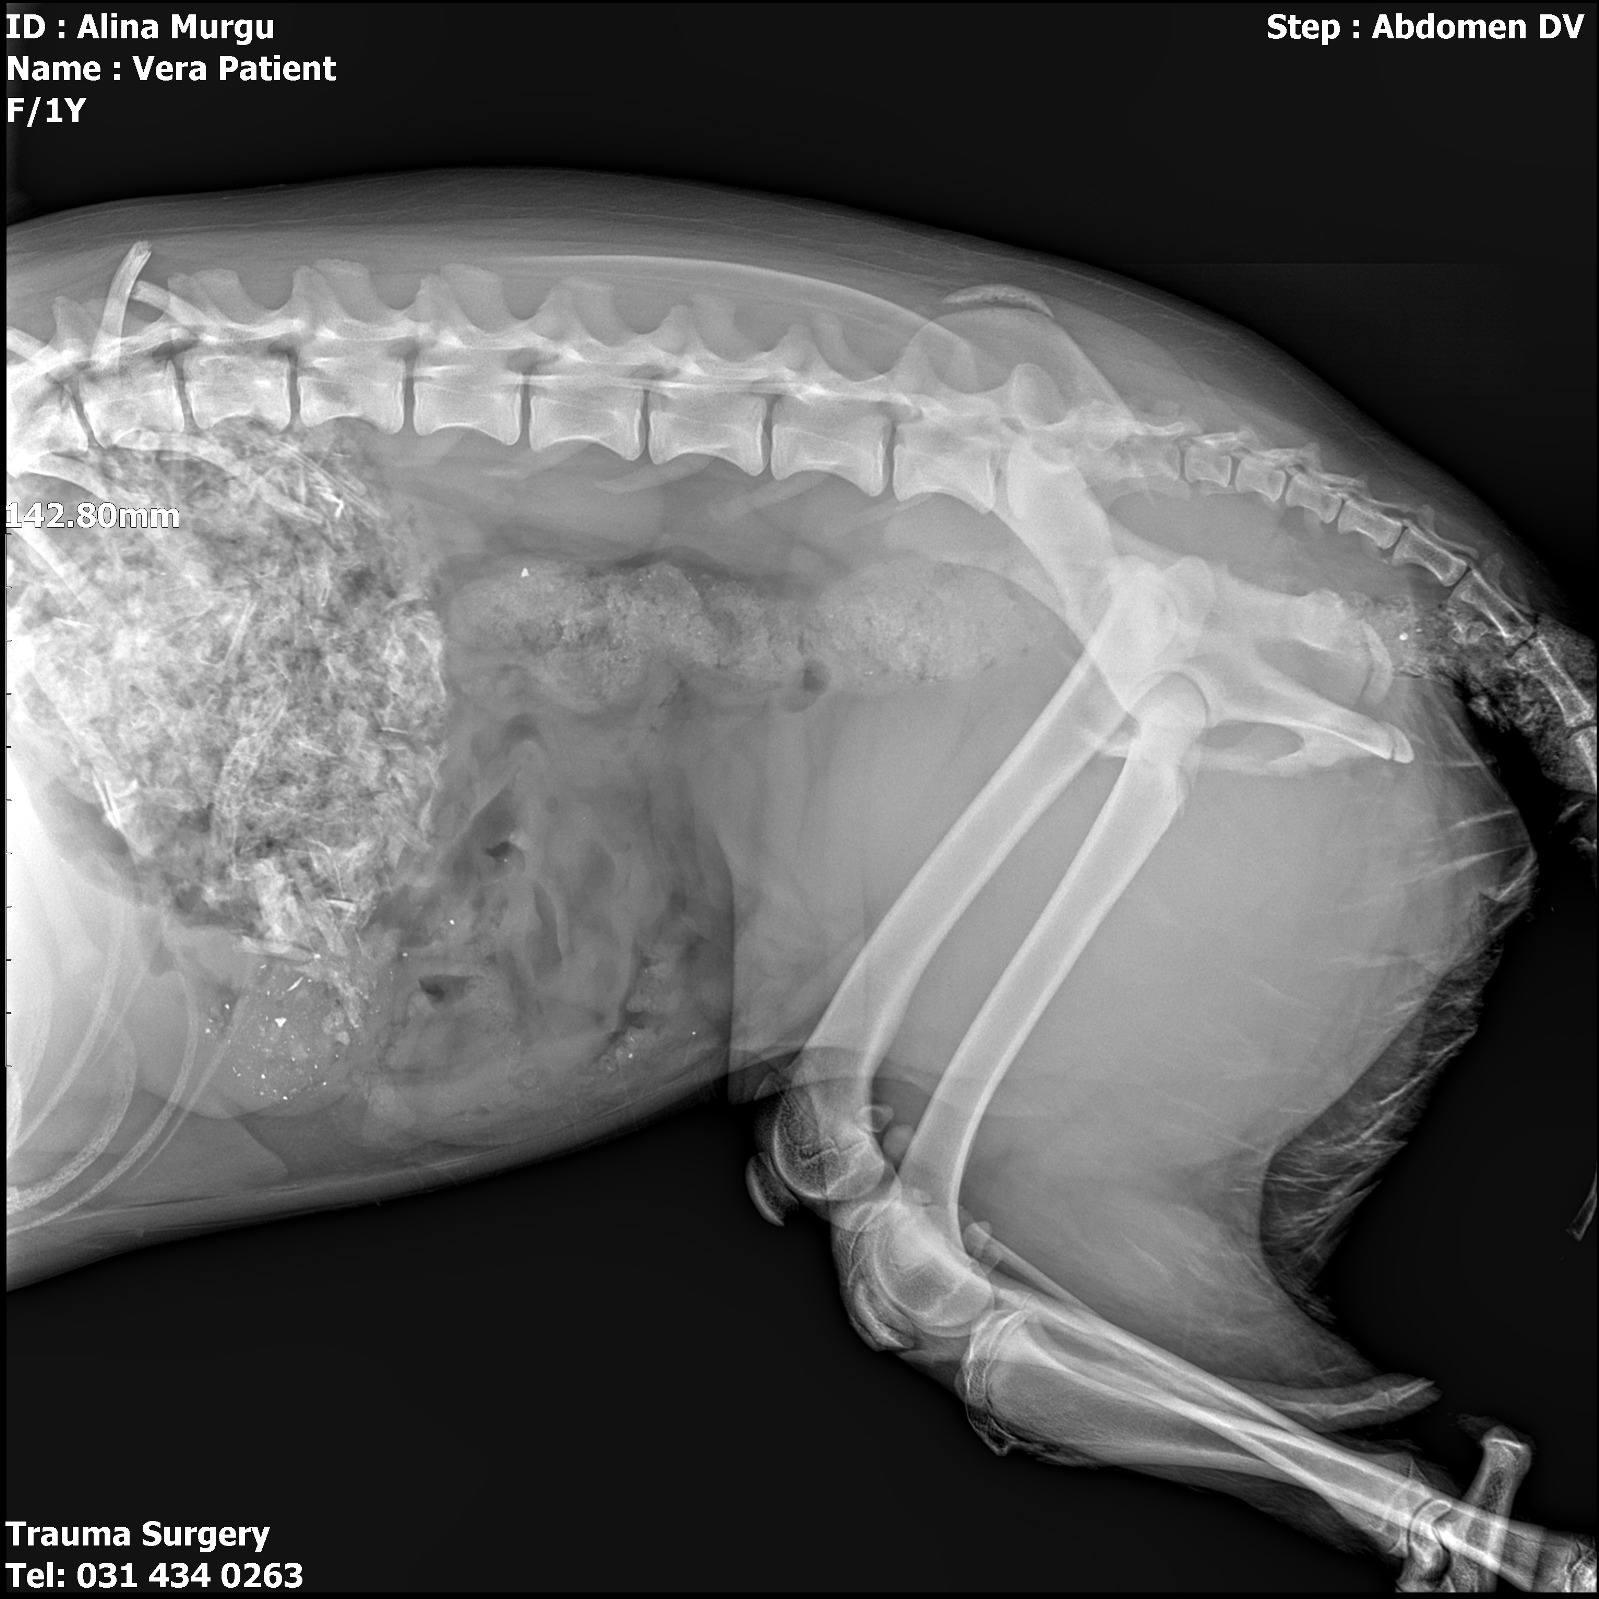

Le diagnostic est lourd : cette chienne courageuse souffre d’une fracture du bassin et a quatre côtes cassées. Face à ces blessures qui menacent sa vie et sa mobilité, le verdict des vétérinaires est sans appel : une intervention chirurgicale est nécessaire, et elle a eu lieu le jour même.